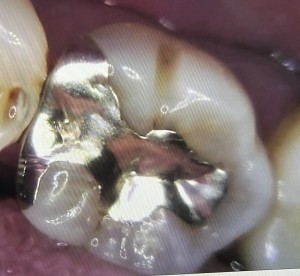

以前から口を開けたときの歯の色が気になっていたとのことで、銀歯を白くしたいとのご希望で来院されました。

治療前の歯は以下のような状態でした。

1日目 虫歯を取り除き、プラスチックで成形した後、型取りを行います。

2日目 セラミックを接着性のセメントで装着します。

治療後に痛みやしみる症状はありませんでした。今回の患者様は、虫歯を早期発見でき、神経を取らずに修復できたことを大変喜んでいらっしゃいました。